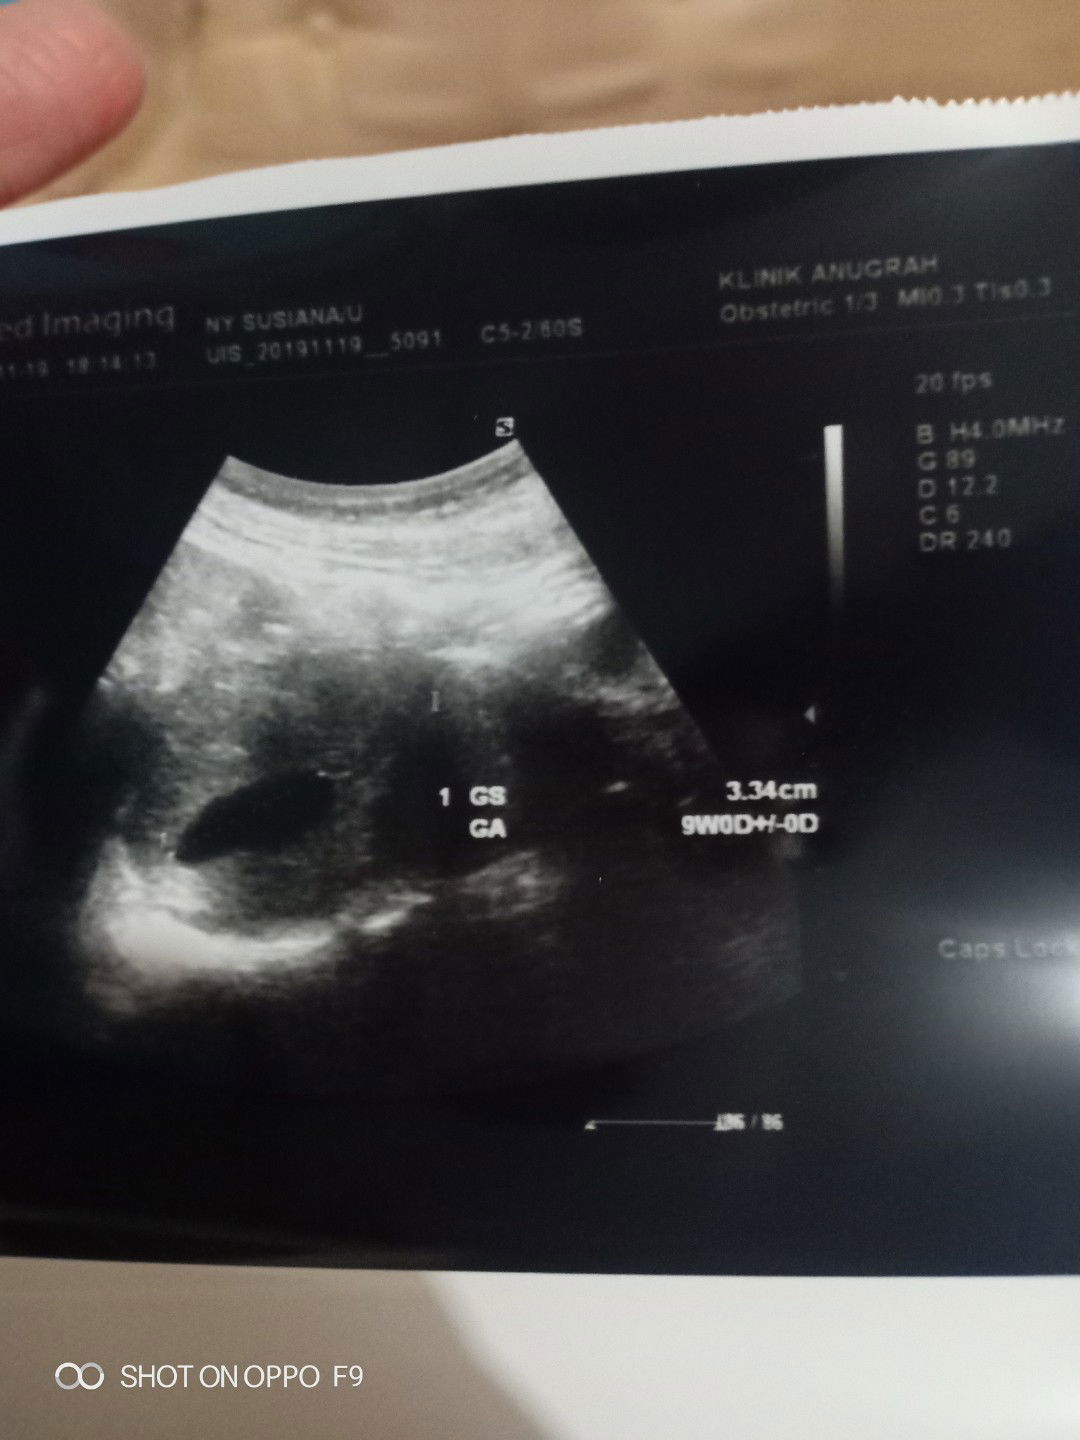

kehamilan kosong padahal udh 9week ?

Hari ini saya baru sja usg,tapi dr nya bilang masih belom nampak janinnya, 2minggu di suruh balik lagi semoga janinnya ada gitu kata drnya. Cma drnya tadi bilang takutnya hamil kosong,ada gk Bunda yg pernah kyak gini?? ???. Dan udh 1 minggu ini saya ngeflek trus bun dan juga 4hari trakhir ini fleknya banyak ? saya sedih bun hancur hati saya apa lg pas dengar drnya bilang klo 2 mggu lg masih kosong harus di kuret .